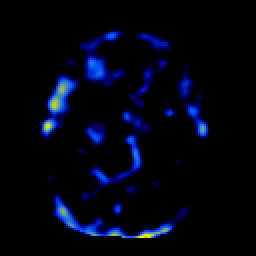

SPECT TL Study #1 -- Slice #23

[Home][Help][Clinical][Tour 1][Tour 2][Tour 3] Slice 23